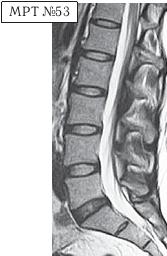

МРТ № 2

На МРТ № 2 — грудной отдел в состоянии «норма»

Грудной отдел должен иметь нормальную степень кифоза (угол кифоза по Stagnara формируется линией, параллельной замыкательным пластинкам ТIII и ТXI= 25°). Позвоночный канал на грудном уровне имеет округлую форму, что делает эпидуральное пространство узким почти по всей окружности дурального мешка (0,2–0,4 см), а на участке между TVI и ТIX он наиболее узок. Сагиттальный размер: ТIХI = 13–14 мм, ТXII = 15 мм. Поперечный диаметр: > 20–21 мм.

Высота межпозвонковых дисков: самая меньшая на уровне ТI, на уровне ТVIХI приблизительно 4–5 мм, наибольшая на уровне ТХIХII.